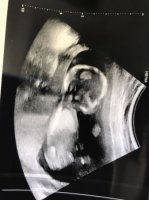

15 uker + 1 eller 2 dager, 120 g, 10 cm

Aktiv liten frisk baby som sprellet og snudde seg rett som det var! Hun var usikker, men mest sannsynlig er det en liten gutt. En måned til OUL og (kanskje) en endelig bekreftelse på det bildet ble sidelengs her, men SE! Det er jo et lite miniatyrmenneske inni der!